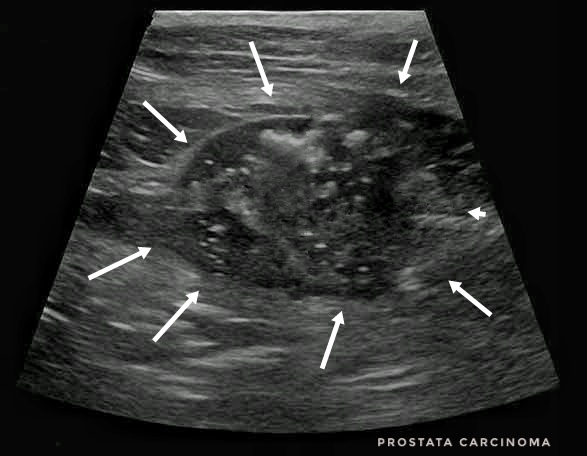

A prosztata megnagyobbodása esetenként (az állat méretétől és a prosztata megnagyobbodásának mértékétől függően) rektális tapintással, hasi röntgennel, vagy még inkább ultrahanggal diagnosztizálható. A méretnövekedés okának felderítésére a citológiai mintavétel teremt lehetőséget, melyet rendszerint katéteres technikával végzünk. Ezen túl érdemes lehet még vizelet citológiát és mikrobiológiai vizsgálatot végezni.

A 3 dimenziós képalkotó vizsgálatoknak (pl. CT, MRI) itt általában az áttétkeresésben van szerepük. A prosztata állományának kalcifikációja (meszes gócok) a tumoros folyamat jellemzője, ahogy a CT-n vagy röntgenen a környező csigolyatesteken látható csontoldódás is erre utal.

Prosztata carcinoma